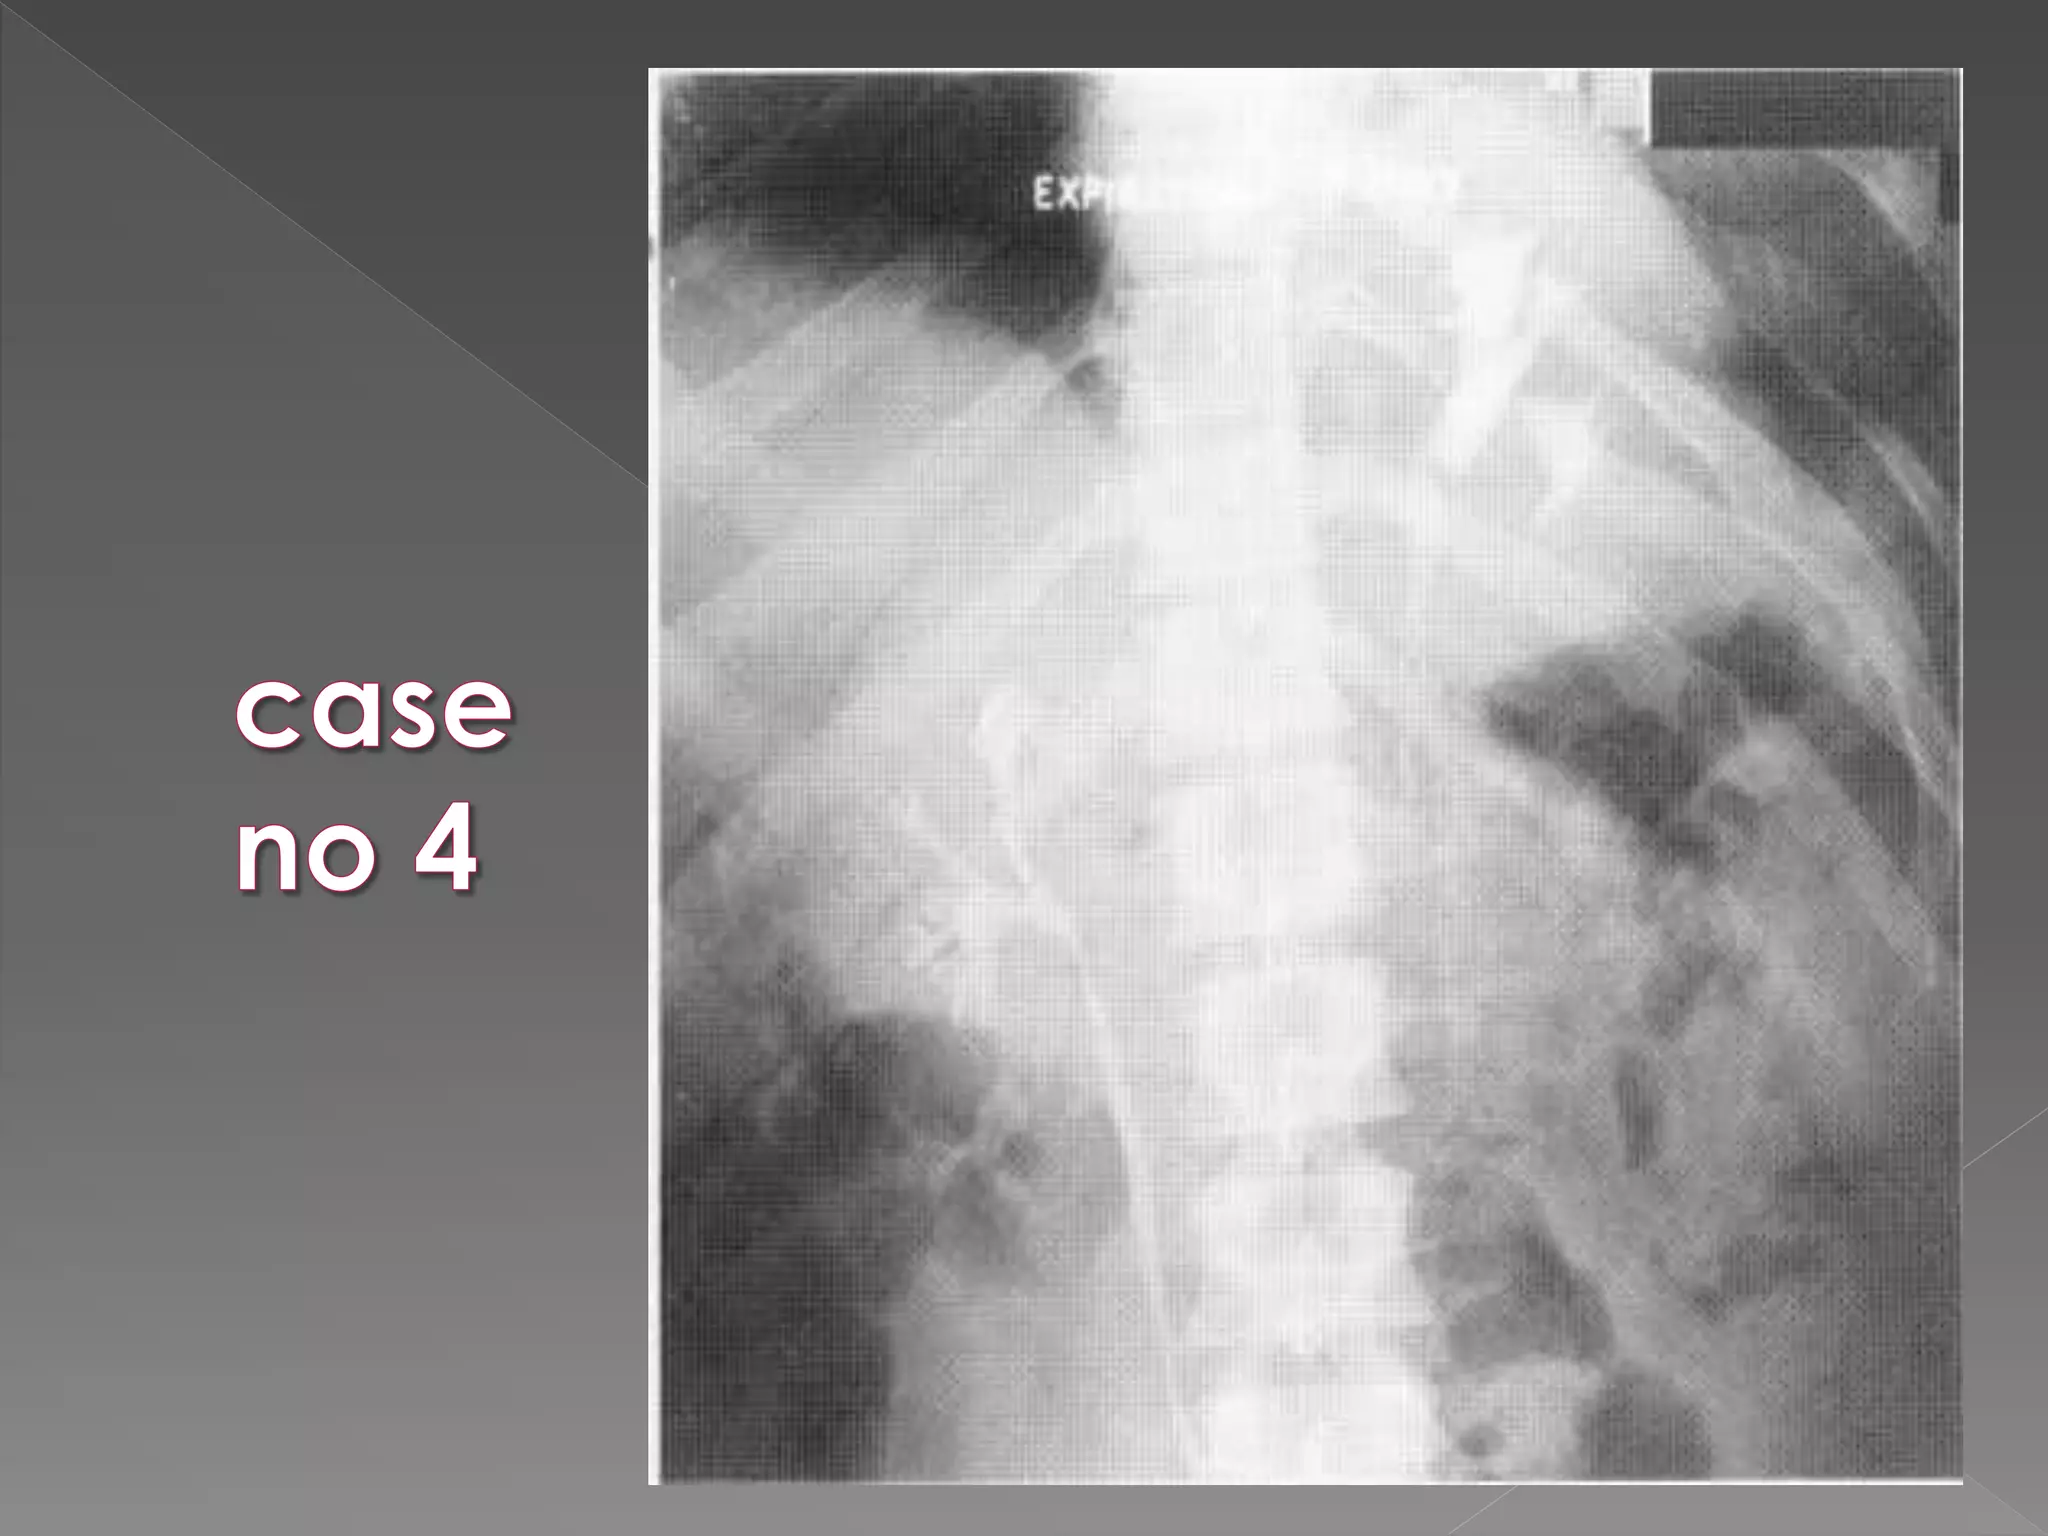

 Acute Obstruction: There is delay in opacification of the collecting system.  Delay may be considerable up to 24 hrs or more.  It is then necessary to perform additional films

 Time intervalb/w films is doubled 0.5 hrs/ 1 hr/ 2 hrs/ 4 hrs/ 16 hrs/ 24 hrs as necessary.  To minimize the radiation exposure If there is no opacification at 30 mins it is usually unhelpful to perform next film before 4 hrs